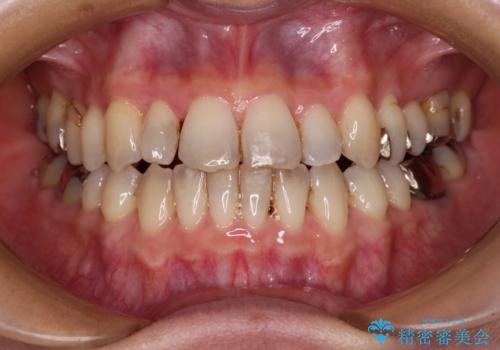

急速拡大装置 前歯の反対咬合をインビザラインで改善

- 前歯の反対咬合を気にして来院された患者様です。

上顎骨の幅が下顎骨よりも小さいので、拡大装置により骨幅を広げて上下関係を改善すると同時にワイヤー矯正で反対咬合の改善を図り、その後インビザラインにて歯並びを整えることとしました。

上顎前歯の矮小歯は矯正治療の途中でオールセラミッククラウンを装着し、左右のバランスを整えることとしました。

急速拡大装置の使用により奥歯の咬み合わせが劇的に変わり、その変化を利用して反対咬合を改善することができました。

治療期間中は奥歯が咬み合わず、食事が取りにくいなどの不都合がありましたが、最終的にはきれいに整えることができました。